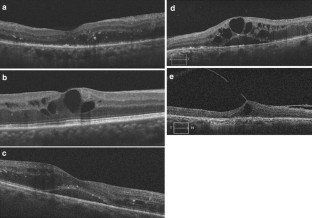

Fig. 2

Fig. 3